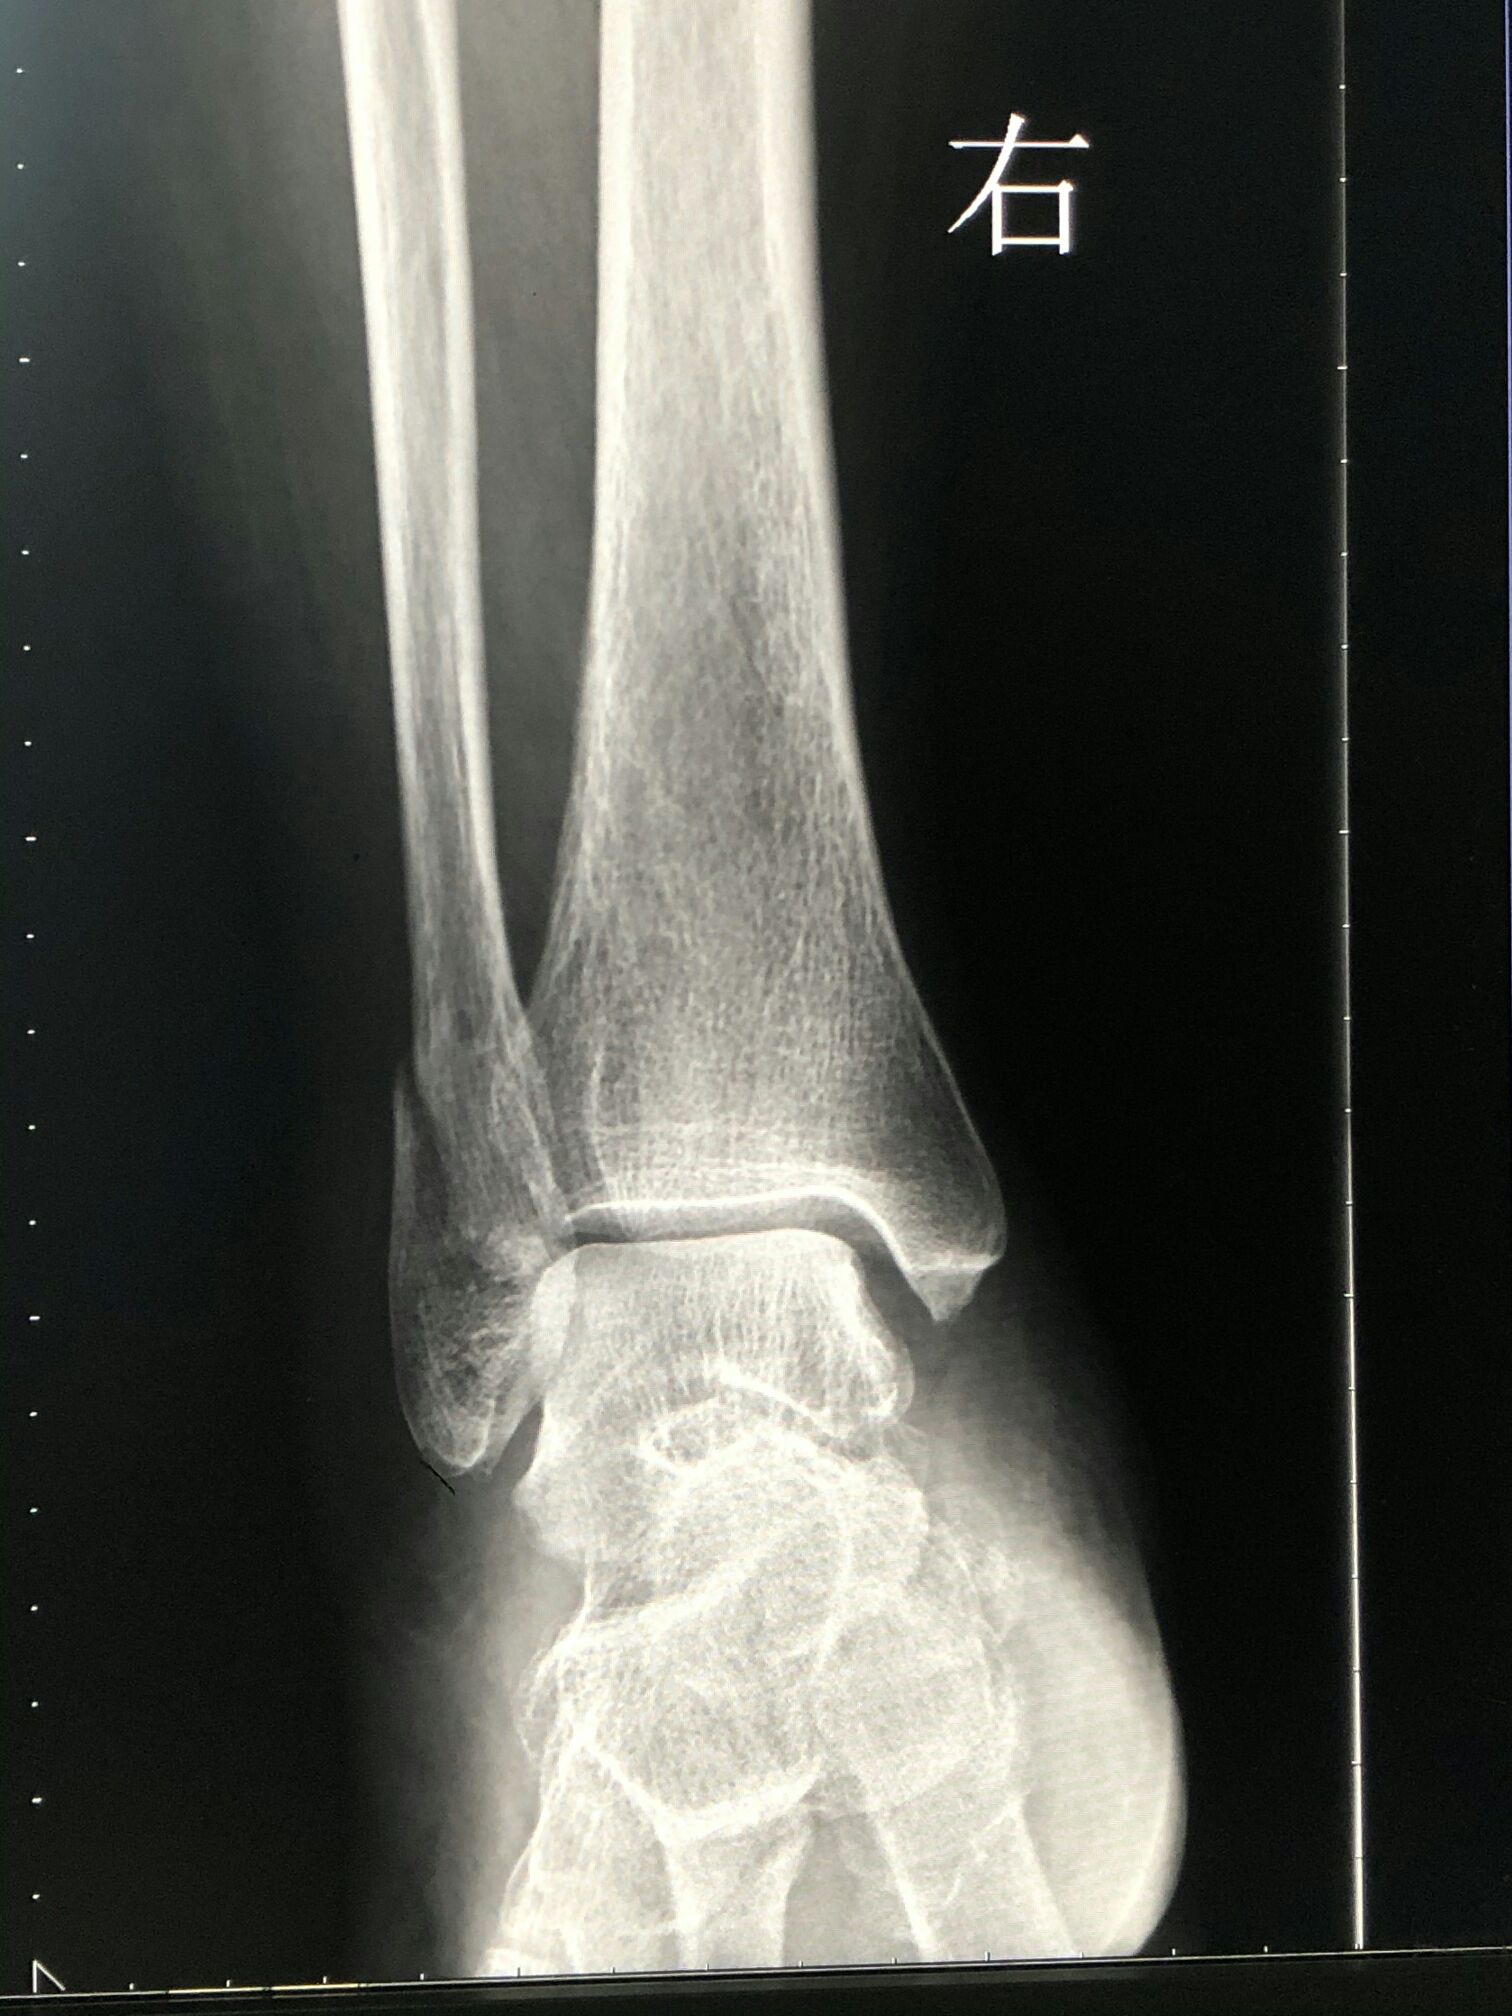

摔了一跤,骨折。